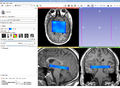

Project Title: Generation of a hybrid MR-Spectroscopic (MRS) dataset under 3DSlicer

Generating a hybrid MR-Spectroscopic (MRS) dataset under 3DSlicer that can be used for fusion with the anatomic dataset under iPlan of BrainLAB in AMIGO. A hybrid MR-Spectroscopic dataset can for example be used for biopsy targeting in brain tumors. Besides, the metabolic concentrations and ratios can help to diagnose lesions.

Try to process MRS data with the MRSI module from Bjoern Menze developed at a previous project week. The module interfaces SIVIC, which is an open-source standards-based software framework and application suite for processing and visualization of DICOM MR Spectroscopy data.

Loaded/integrated processed chemical shift-MRS data from Uni. Marburg into Slicer4.